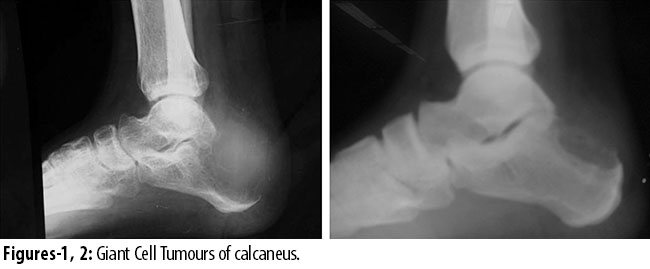

There were 240 cases of giant cell tumour but only 13(5.4%) related to foot bones. Of them, 8 (3.3%) were females and 5(2.0%) males. The mean age was 25 years (SD 10.59) (range: 17-38 years). In 7 (2.9%) cases lesion was in metatarsals, 2(0.8%) cases in phalanges, 3(1.2%) cases in calcaneus and 1(0.4%) case in talus (Figure-1 and 2).